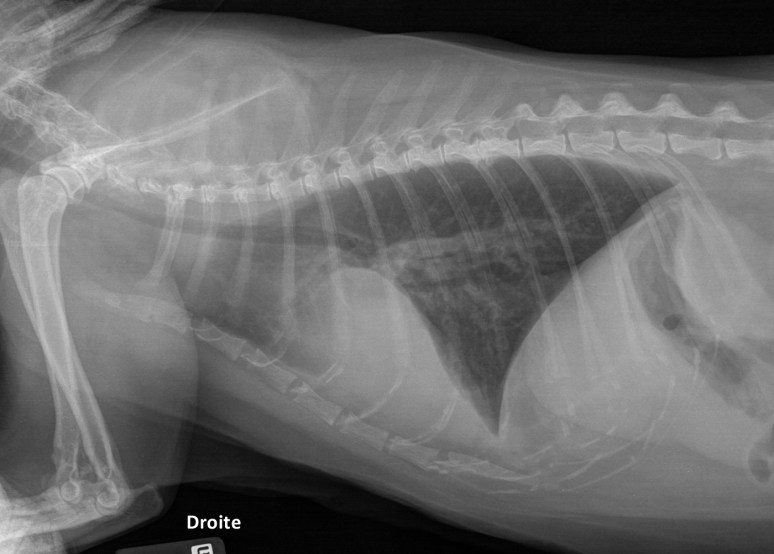

Signalement: chat domestique, femelle opérée de 12 ans

Histoire clinique: anorexie, perte de poids, vomissements